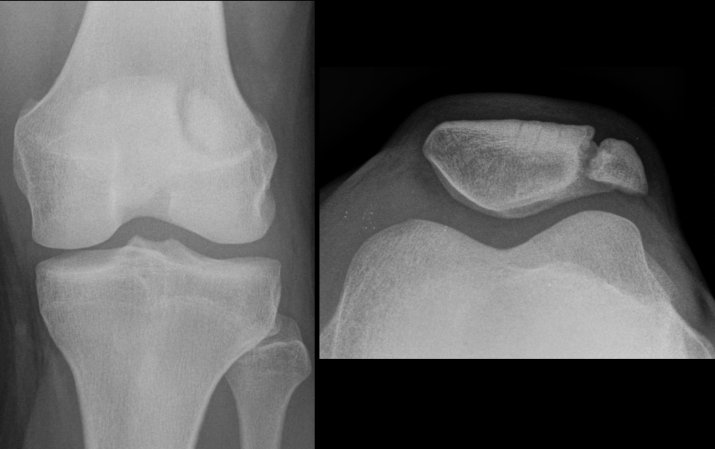

Our understanding of the skeleton’s many roles has expanded a lot thanks to evolving imaging technologies, Black says. They allowed scientists over the past 125 years to see inside living bodies and watch bone in action. The first glimpse at living bones in situ came in 1895, when X-ray inventor Wilhelm Rontgen took a picture of his wife Anna Bertha Ludwig’s hand bones. (History did not record what Ludwig thought about seeing her own hand, complete with wedding ring.)